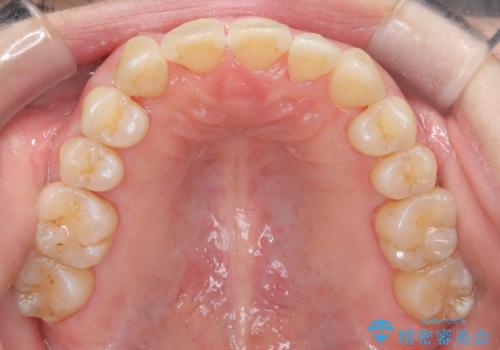

【インビザライン】ずれた前歯の噛み合わせをなおしたい

- 前歯の噛み合わせが悪いことを主訴に来院されました。

歯周病も併発していたため、歯牙への負担が少なくなるように治療計画をたて、インビザラインにて治療を完了しました。

矯正開始前に半年間、歯周治療を行ってからインビザラインを装着しています。